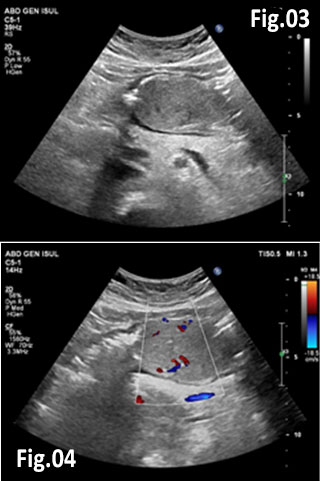

GISTs are rare mesenchymal neoplasms of the digestive tract [1,2]. They have been documented in all parts of the gastrointestinal tract, but are most common in the stomach and small intestine, followed by colo-rectum, mesentery, and esophagus [1,2]. However, the synchronous occurrence of lung cancer and GIST is extremely rare [3]. The incidence of GIST coexisting with additional malignancies is 9% to 27%, and primary lung cancer in GIST patients is 0.5%-1.2% [3]. A 75 year old woman with a smoking history for >30 years was diagnosed with advanced stage of left lung primary adenocarcinoma by chest computed tomography (CT) and bronchoscopy with sampling in February 2015 (Fig.1, Fig.2). The patient started Erlotinib 150 mg/day. In September 2015 the patient was admitted with vague abdominal pain and postprandial vomiting. Physical examination, routine blood, urine and stool investigations were unremarkable. Abdominal ultrasound detected an oval, homogenous, hypoechoic lesion 6/5/4 cm, arising from the submucosal layers of the gastric wall (Fig 3). The color Doppler demonstrated neovascularization (Fig 4). Except for 3 small simple liver cysts, no other abnormalities were present. Upper endoscopy and endoscopic ultrasound (EUS) revealed a large oval, slightly lobulated mass, hypoechoic 6x5cm between incisura angulars and greater curvature of the gastric body, originating from the 4th layer of the wall (muscularis propria). The tumor was slightly “dumbbell” shaped, protruding in and outside the stomach lumen, with several irregular hypoechoic zones and micro cysts within, looked encapsulated without infiltration of the surrounding tissues and pathologic abdominal lymph nodes (Fig. 5). A contrast-enhanced ulstrasound (CEUS) and contrast-enhanced computed tomography (CECT) of the abdomen additionally characterized the lesion and excluded liver metastases. (Fig. 6, Fig. 7) Percutaneous true-cut biopsy of the lesion was performed (18G, two separate puncture sites) (Fig 8). The immunohistochemical analysis revealed epithelioid-type GIST, diffusely positive for c-kit (CD117), with a weak focal expression of S-100 (Fig. 9). Due to life expectancy defined by the unresectable advanced lung cancer, the patient was not indicated for resection of the gastric GIST. Imatinib (Glivec) 400 mg/day was started as a “co-therapy” to Erlotinib in November 2015. After 12 months of co-treatment, a good control of both tumors was achieved. CT and abdominal ultrasound showed the gastric lesion was slightly shrunk on therapy, with large central necrosis (Fig. 10). The patient is being followed up.

Figure 3: Abdominal ultrasound: a solid hypoechoic oval tumor arising from the gastric wall

Figure 4: Color Doppler: Tumor neovascularization